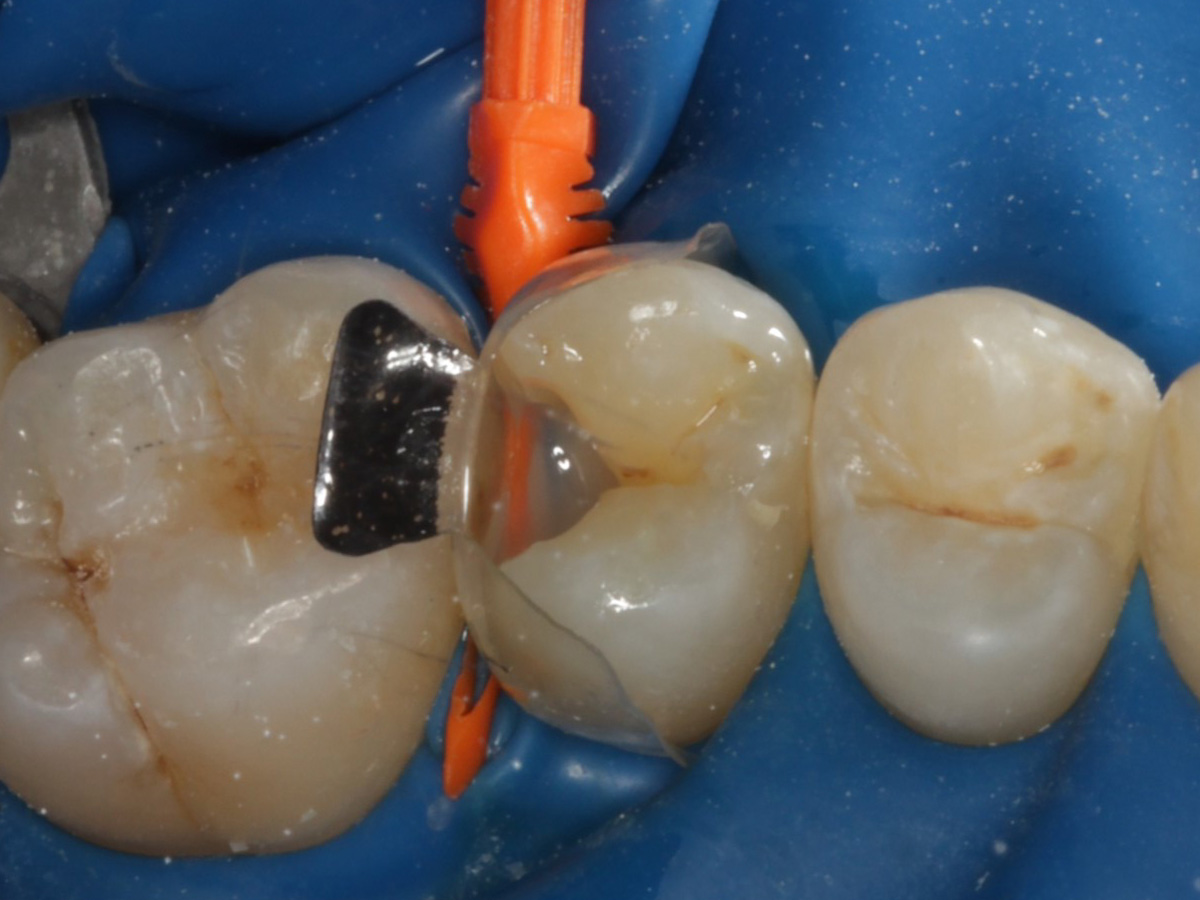

Abbildung 10

Nach Applikation der Matrize: Evolve Schwarz Prämolar- 7 mm; Schmelzätzung